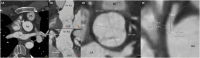

Background: After the arterial switch operation (ASO) for transposition of the great arteries (TGA), neo-aortic dilatation and coronary arterial anomalies, especially an interarterial course and acute coronary artery take-off angle, are commonly found. Long-term follow-up data after ASO is scarce. Aim of this study was to determine the prevalence of neo-aortic dilatation and coronary abnormalities, with special emphasis on acute coronary take-off angle, in adult TGA-ASO patients.

Results: Eighty-one patients, 69 % male and median age 21.0 [18.5-22.8] years, were included. At baseline, maximum neo-aortic diameter was 39.2 ± 5.3 mm; 35 (43 %) patients had neo-aortic dilatation (neo-aortic diameter of >40 mm), 22 (27 %) patients had an acute coronary take-off angle (<30°), and 5 (6 %) patients had an interarterial course of the RCA (2 %) or LCA (4 %). Neo-aortic or coronary artery re-intervention occurred in 10 (12 %) patients. All 10 patients had neo-aortic dilatation or coronary take-off angle of <30° on baseline CTA.

Conclusion: This study reports a prevalence of 43 % of neo-aortic dilatation, 6 % of interarterial coronary course and 27 % for acute coronary take-off angle (<30°) at a median term of 21.0 years post ASO. All patients with a neo-aortic re-intervention or coronary artery re-intervention during follow-up had a maximum neo-aortic diameter of >40 mm or a coronary take-off angle of <30° at baseline CTA. This hypothesis generating study suggests that an active surveillance in patients with neo-aortic dilation and/or an acute angulation of < 30° post ASO might be considered and requires prospective evaluation.